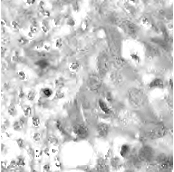

In practice, directly using point annotation for the nuclei segmentation could suffer from the data-imbalance problem due to insufficient supervision information. To alleviate this issue, we adopt the Voronoi diagram [24] and the -means clustering method [25] to generate Voronoi label and cluster label, respectively. Specifically, for Voronoi labels, as shown in Fig. 1, the image is divided into convex polygons based on the point annotations with the assumptions that the point labels are at the nuclei centers and nuclear shapes are convex (even though these assumptions are not necessarily valid). For cluster labels, as shown in Fig. 1, we utilize the -means to obtain more supervision information of nuclei boundary and shape as follows. First, we calculate the distance maps from the point labels by performing distance transform between each pair of points. Second, the distance maps are combined with the original H&E stained images to conduct the -means clustering to divide all pixels into clusters: nuclei, background, and ignored area. The clusters that have maximum and minimum overlap with the point annotations are labeled as nuclei and background, respectively. The remaining one is the ignored class. The introduction of an ignored area allows pixels that cannot be easily determined as nuclei or background with certainty not be forced into either class, ensuring that the clustering can assign correct pixel labels as much as possible [27]. Third, several morphological operations are adopted to refine the cluster label, including connected domain labeling, scattered region removing, morphological opening operation, and binary hole filling.

where and denote the Voronoi label and cluster label of nuclei at the -th pixel, respectively; denotes the prediction of the segmentation network with H-component as input; and (i.e., or ) is the set of non-ignored pixels. As illustrated in Fig. 1, the Voronoi label is used to supervise the network to separate overlapping nuclei, while the cluster label could provide coarse shape and boundary information for nuclei segmentation. In the following, we elaborate the co-training strategy to further provide supervision to the ignored area of the coarse cluster labels, denoted with the blue color in Fig. 1.

where is the -th pixel of the pseudo label, is the set of all pixels, and denotes the predictions of with respect to the H-component . With the training set split into two non-overlapping subsets and , two segmentation networks are trained with the coarse labels (i.e., the Voronoi and cluster labels) by and , respectively, the two networks could transfer knowledge to each other with their respective pseudo labels, so as to compensate for the missing supervision information. However, the segmentation performance may still suffer from the inaccurate cluster label, as shown in Fig. 1. Hence, our next step is to explore an auxiliary colorization task that transforms H-component images back into the original H&E stained images from which more precise nuclei boundaries can be obtained.

To investigate the impact of the proposed co-training and colorization methods, we validate the effectiveness of each module on the MoNuSeg dataset. Considering that Voronoi labels provide more shape supervision information than point annotation, we regard the model that jointly uses the point annotation and the Voronoi label as the baseline, and mainly evaluate the improvement of each module upon this baseline in Table III. Model A utilizes only point annotation and Voronoi labels with cross-entropy loss. For a fair comparison with co-training, we employ two separate models which have the same architectures for co-training and average the predictions of the two models in inference. Model B further adopts the cluster label. It can be seen that the cluster loss is beneficial in segmenting overlapping nuclei, improving the from 60.20% to 72.48% and the AJI from 43.01% to 51.77%, which indicates that simply using the point annotation and the derived Voronoi labels cannot provide sufficient supervision for the nuclei segmentation due to the lack of boundary and area information. However, the cluster labels generated by the -means algorithm cannot separate close nuclei which would introduce distraction to the training process, as shown in Fig. 1. To address this challenge, Model C utilizes the co-training strategy that the two models facilitate each other in a bootstrapping way to eliminate the distraction brought by the cluster labels. As expected, co-training brings a consistent improvement in all metrics, including an 1.19% increase to AJI. We believe that co-training compensates for the loss of supervision information in the uncertain regions in the cluster label, and the probability map with EMA by another model provides more precise and robust supervision in the nuclei boundary. Visualization of the segmentation results can be found in Fig. 3, and it can be seen that with the co-training strategy, the model can achieve more accurate results, especially in the nuclei boundary area. Model D involves colorization as a proxy task to implicitly learn to be self-aware of the nuclei boundary. Instead of directly coloring the H-component (Fig. 4(a)) to the H&E map (Fig. 4(d)), we use the segmentation probability map (Fig. 4(b)) as the input of the colorization network, which can help us to boost the segmentation accuracy. The experimental result shows that integrating the colorization tasks could not only improve the by 1.54% and AJI by 3.24%, but also promote Acc by 0.18% without dropping F1 score, proving that the colorization task has a significant guiding effect on nuclei segmentation. In Fig. 4(c), the improvement of colorization in the nuclei boundary area can also be observed. In general, the four modules used in our method have complementary advantages. By minimizing the weighted sum of the four losses, the proposed framework can distinguish between nuclear and non-nuclear to the greatest extent.